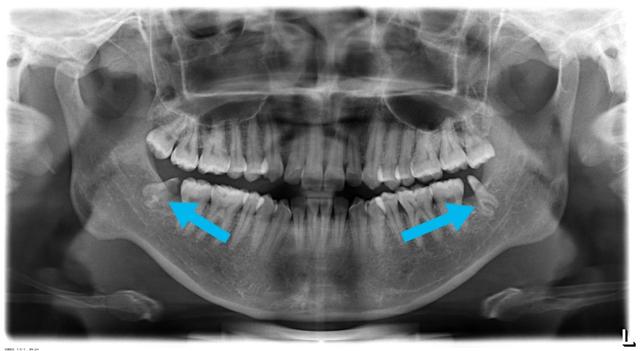

1、拔牙之前一定要拍全景片(甚至要拍ct,早年口腔CT还没有普及),不愿意拍片者,不敢拔

2、牙根离神经管很近的智齿,建议用两个步骤来处理,否则不拔